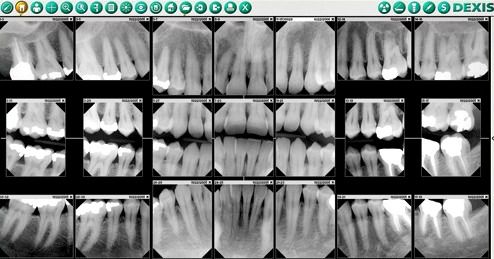

X-Ray Certification for Dental Assistants is essential. This course prepares students for employment as a Dental Assistant by training them in both X-Ray Preparation and X-Ray Exposure, later allowing them to gain their certification. Our X-Ray Certification for dental assistants course includes education about radiation safety, production of x-rays, and oral radiography (digital and traditional), along with learning how to operate dental x-ray equipment under the supervision of a certified dentist.